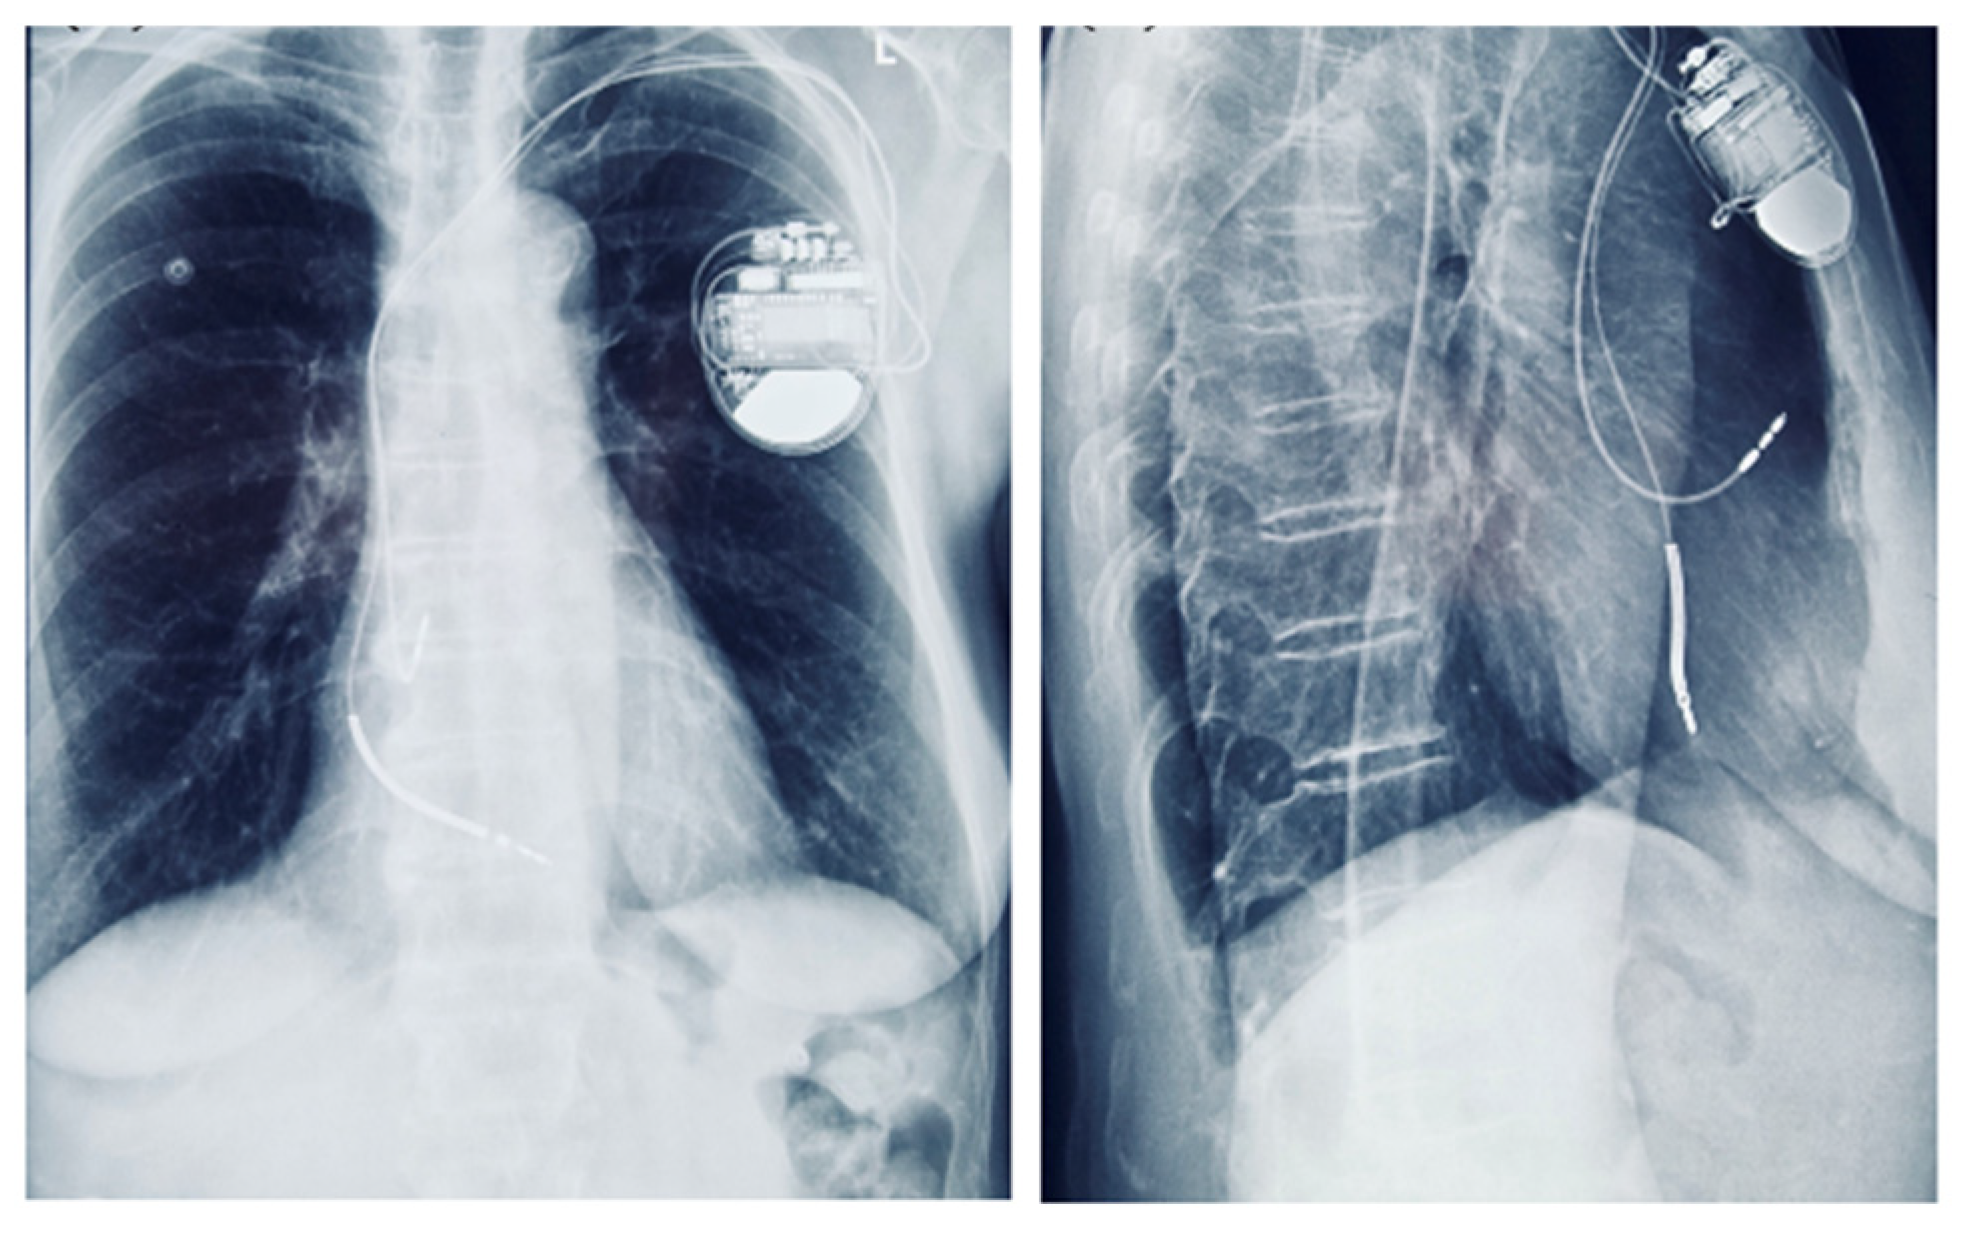

Although the patient had no sustained VT and no LGE on CMR, implantable cardioverter-defibrillator (ICD) implantation was justified by the presence of multiple high-risk features. Following Heart Team discussion, an ICD was implanted for primary prevention of sudden cardiac death, in the context of arrhythmogenic mitral valve prolapse (AMVP) with high-risk features (Figure 9). Moreover, given the additional need for beta-blocker therapy and the patient’s baseline bradycardia, a dual-chamber ICD was selected to provide both arrhythmic protection and pacing support. The presence of bradycardia, together with the requirement for antiarrhythmic medication, represented an additional factor influencing the decision for ICD implantation.

Figure 9.

Chest radiograph showing a dual-chamber implantable cardioverter-defibrillator (ICD) in anteroposterior and lateral views.